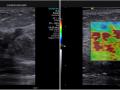

Elastografia de tumor multifocal da mama

A elastografia é uma tecnologia associada à ultrassonografia que permite discriminar os tecidos avaliados entre macios (azul), intermediários (verde) e duros (vermelho). Os nódulos de mama malignos são mais frequentemente duros (vermelhos).

No caso ilustrado, a paciente apresentava dois nódulos com diagnóstico de carcinoma ductal invasivo (tipo não especial) no mesmo quadrante da mama, o que é definido como multifocalidade.